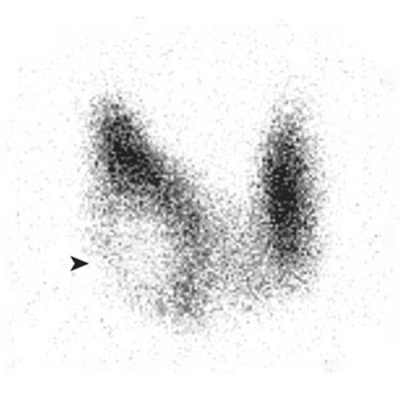

Screening for Thyroid Cancer

Interview with Charles Landefeld, MD, author of Screening for Thyroid Cancer: US Preventive Services Task Force Recommendation Statement